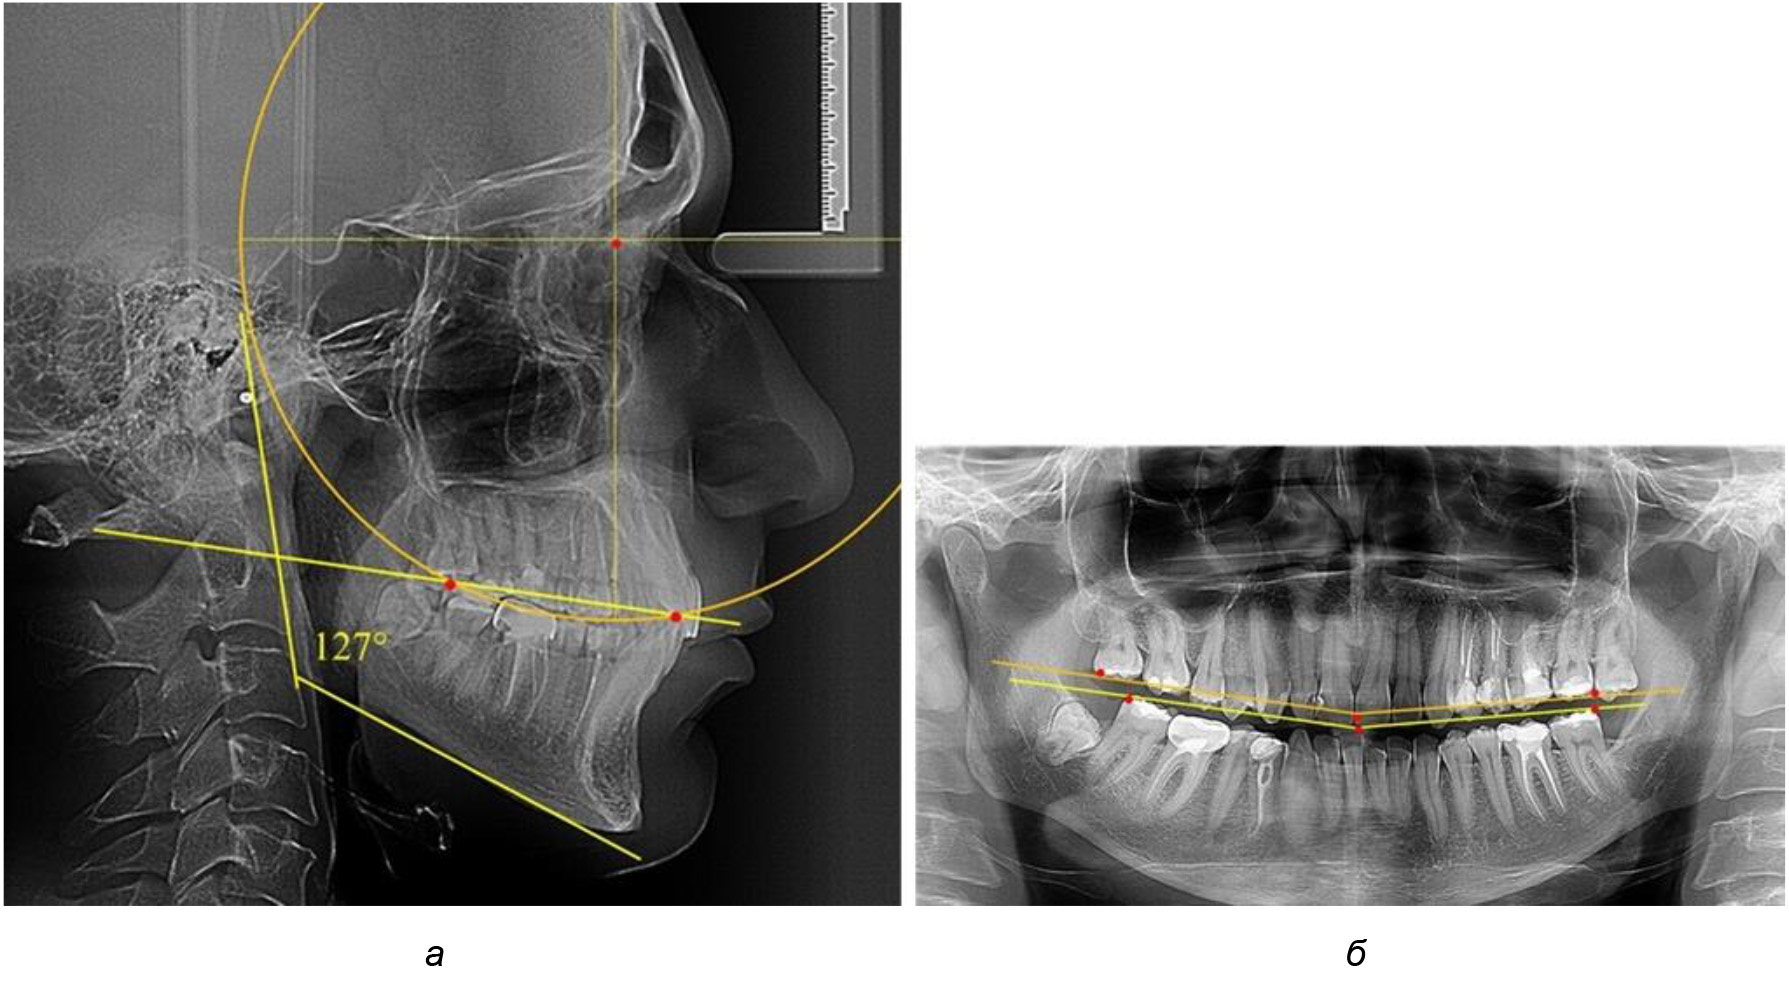

У людей с аномалиями окклюзии по сагиттали в 1-й подгруппе обследовано 9 человек. Обращает на себя внимание увеличение глубины кривой Spee, что нами расценивалось, как патологическая форма кривой линии окклюзии.

Глубина кривой Spee в среднем по 2-й подгруппе составила (5,69 ± 1,57) мм, что было достоверно больше, чем у людей с физиологической окклюзией (р ˂ 0,05). Достоверных различий с показателями, полученными при анализе ТРГ и ОПТГ, нами не отмечено (р ˃ 0,05). Отношение радиуса окружности к сагиттальному размеру окклюзионной линии в среднем по подгруппе составляло 1,372 ± 0,042 и не соответствовало числу Фибоначчи, что может быть использовано в качестве диагностического критерия определения патологической формы кривой Spee. После лечения пациентов техникой «прямой» дуги было отмечено незначительное увеличение сагиттального размера окклюзионной лини в среднем на (2,12 ± 0,77) мм. Однако окклюзионная линия практически касалась окклюзионного контура всех жевательных зубов, и отмечалось практически полное отсутствие кривой Spee.

Таким образом, проведенное лечение техникой «прямой» дуги способствует нормализации окклюзионного равновесия и торку передних зубов, однако не соответствует оптимальному окклюзионному статусу, характеризующему физиологическую окклюзию. При этом величина нижнечелюстного угла оставалась на прежнем уровне (рис. 5).

Рис. 5. Особенности ТРГ при патологической кривой Spee до лечения (а) и после лечения (б) техникой «прямой» дуги

Во 2-й подгруппе 2-й группы было обследовано 7 человек.

Указанная величина не имела достоверного отличия с 1-й подгруппой (р ˃ 0,05), что определяло однородность групп по количественному признаку.

Обращает на себя внимание, что глубина кривой Spee в анализируемой подгруппе практически не отличалась от показателей, полученных у людей с физиологической окклюзией, и составляла (4,23 ± 1,58) мм. Отношение радиуса окружности к сагиттальному размеру окклюзионной линии в среднем по подгруппе составляло 1,623 ± 0,02 и соответствовало числу Фибоначчи.

После лечения пациентов техникой «прямой» дуги, так же как и в 1-й подгруппе, было отмечено увеличение сагиттального размера окклюзионной лини в среднем на (2,38 ± 0,83) мм. Окклюзионная линия практически касалась окклюзионного контура всех жевательных зубов, и отмечалось практически полное отсутствие кривой Spee, так же как и у людей 1-й подгруппы 2-й группы (рис. 6).

Рис. 6. Особенности ТРГ при оптимальной кривой Spee до лечения (а) и после лечения (б) техникой «прямой» дуги

Таким образом, проведенное лечение техникой «прямой» дуги способствует нормализации окклюзионного равновесия и торку передних зубов, однако не соответствует оптимальному окклюзионному статусу, характеризующему физиологическую окклюзию. При этом величина нижнечелюстного угла оставалась на прежнем уровне.